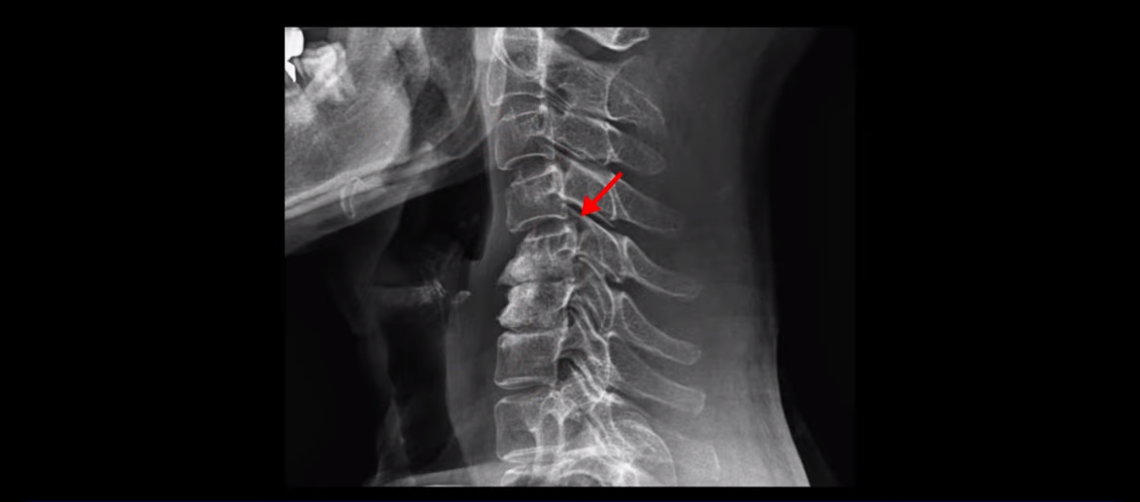

이분 목 X-ray를 보면 역C자형의 목에 전방전위도 보이고,

두 마디의 디스크가 거의 닳아서 뼈들이 거의 붙어 보입니다.

목도 많이 휘어 보입니다.

그래서 오른쪽 신경 가지가 빠져 나가는 추간공 2개와